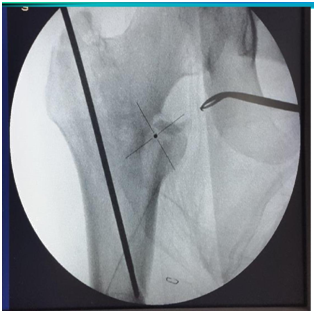

Entry point to be at tip with medial bias

In AP view entry point to be more medial. This allows 2 screws in head in good position (Figures 11&12).3

Figure 12 Entry point by femur finder, Cannulated awl. Curved awl can ensure entry medial to GT and reaming parallel to lateral cortex.